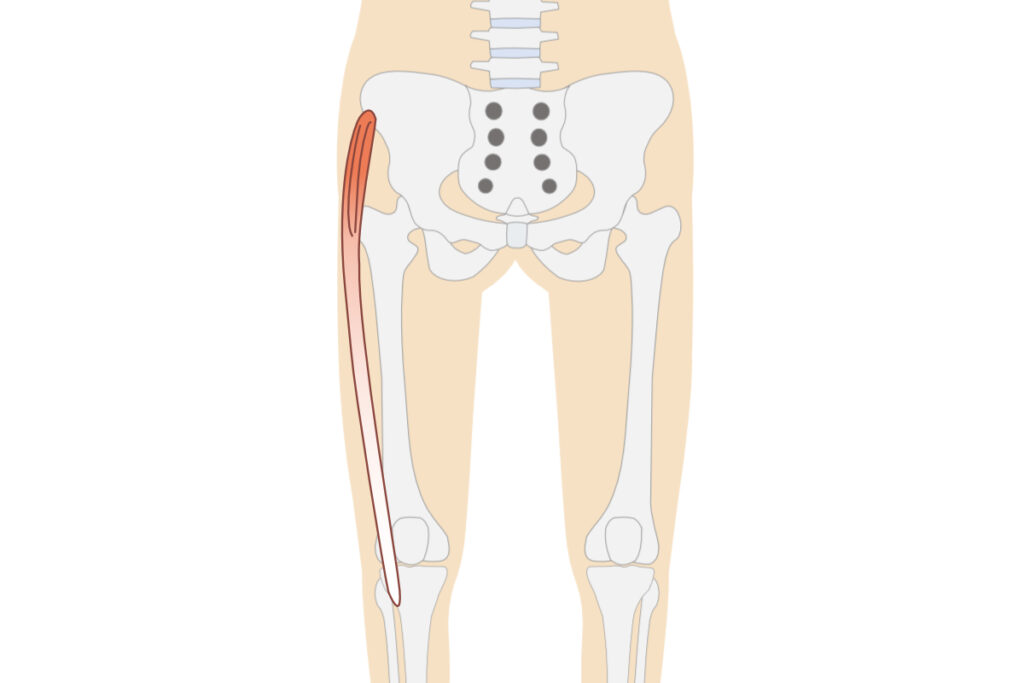

膝の痛みの原因になりやすい筋肉の例

大腿筋膜張筋

膝の痛みの原因になりやすい部位を中心に刺激

大腿筋膜張筋

刺激するポイントは個人差があり、その日の体調によっても変化します(イラストは参考図)